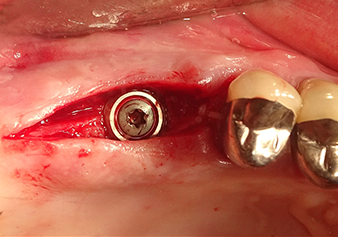

Preparazione e accrescimento della sede dell'impianto

Dopo un controllo intermedio (Fig. 4) è stata eseguita un'ulteriore fase di preparazione (Fig. 5). Lo strumento idraulico Z35P è stato utilizzato in un secondo momento per sollevare la membrana sino alla posizione desiderata (Fig. 6 e 7). In seguito alla suddetta operazione, si è proceduto ad una ulteriore preparazione piezochirurgica della sede dell'impianto conclusasi con l'applicazione della fresa e della fresa a spallamento sul diametro dell'impianto di 4,8 mm. Il materiale di rinforzo (dimensione delle particelle di ca. 0,8 - 1,6 mm) è stato introdotto sotto la membrana di Schneider prima che venisse inserito l'impianto (Fig. 8).

Impianto e ricostruzione protesica